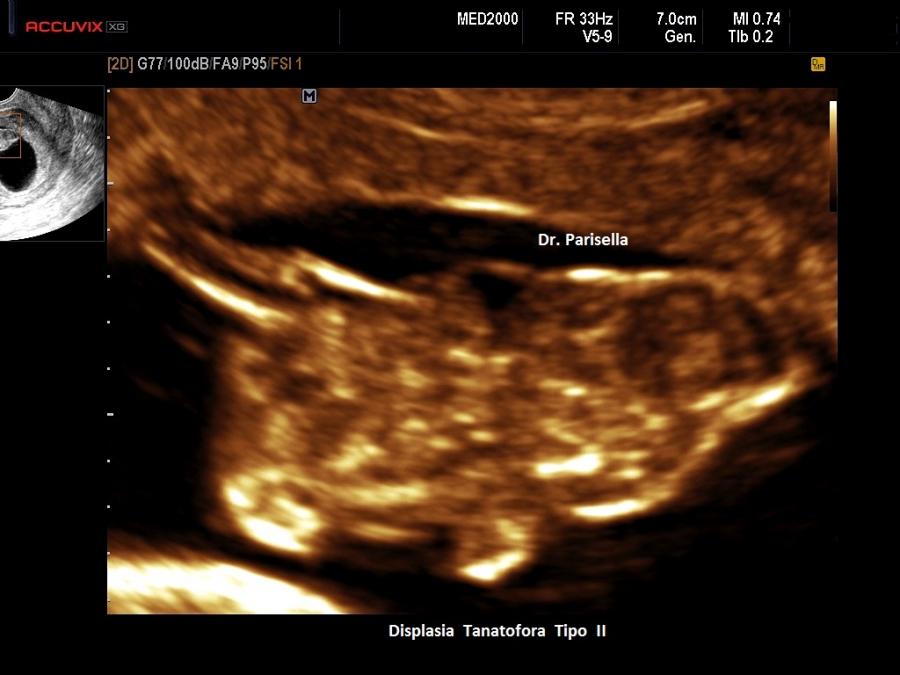

Un altro dato da valutare è il grado di curvatura ossea; le due principali condizioni che possono presentare in epoca prenatale un incurvamento delle ossa lunghe sono l'osteogenesi imperfetta e la displasia tanatofora tipo I (femori a cornetta di telefono).

Per quanto riguarda il rachide la Platispondilia (comunque non facilmente evidenziabile ecograficamente) è presente nella Displasia Tanatofora e nella Displasia Metatropica. Nell'Acondrogenesi tipo I si ha scarsa ossificazione dei corpi vertebrali e costantemente non si visualizza il sacro.

Macrocefalia/Macrocrania è presente nella Acondroplasia, nella Displasia Tanatofora ( il tipo II è caratterizzato da “cranio a trifoglio” ), nell'Acondrogenesi. L'idrocefalia può essere una complicazione dell'Acondroplasia, dell'Osteogenesi Imperfetta e della Displasia Metatropica. Un cranio di consistenza molle (ossa wormiane) è sintomo costante di Osteogenesi Imperfetta anche se può essere presente in altre condizioni quali l'ipofosfatasia, la displasia cleido-cranica, etc. Nell'Ipofosfatasia vi può essere una aumentata ecogenicità della falce cerebrale.